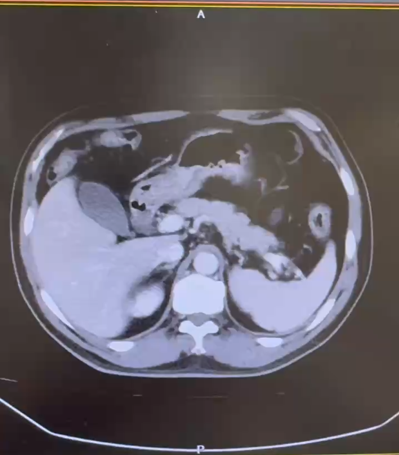

CT:1. 左肾下极占位性病变:肾 CA? 2. 双肺多发囊肿;3. 双肾小结石;4. 肝 S4 段强化灶;5. 肝多发囊肿。

CT:1. 右肾癌伴右肾静脉受累,侧支循环形成;2. 右肾上腺结合部结节灶,转移可能;3. 右输尿管上段管壁局部增厚:侵犯?4. 左肾囊肿。

PETCT:1. 右肾中-下份混合密度软组织肿块,糖代谢轻度升高,SUVmax6.4, 右肾内糖代谢稍增高灶,SUVmax3.8,右肾癌合并肾静脉瘤栓形成;2. 右肾上腺结合部低密度灶,糖代谢轻度增高,转移瘤,SUVmax3.1。

CT(2022.1):1. 左肾肿块,肾癌并出血可能;2. 左输尿管上段结石并周围炎症,左肾结石并积水;3. 右肾萎缩;4. 肝囊肿。

CT(2022.7):1. 右肺转移瘤切除术后改变;2. 左肾上腺结节,转移?3. 左肾多发结节,转移瘤?4. 腹膜后淋巴结肿大,转移可能;5. 左肾多发小囊肿。

PETCT(2022.10):1. 左侧肾上腺结节灶,糖代谢增高,转移瘤可能性大;2. 左肾多发结节状突起,糖代谢增高,考虑转移瘤,需结合增强 CT 综合判断;3. 右下肺切除术后,术区未见复发;4. 右侧胸壁局部增厚、糖代谢增高,术后改变?建议追踪。